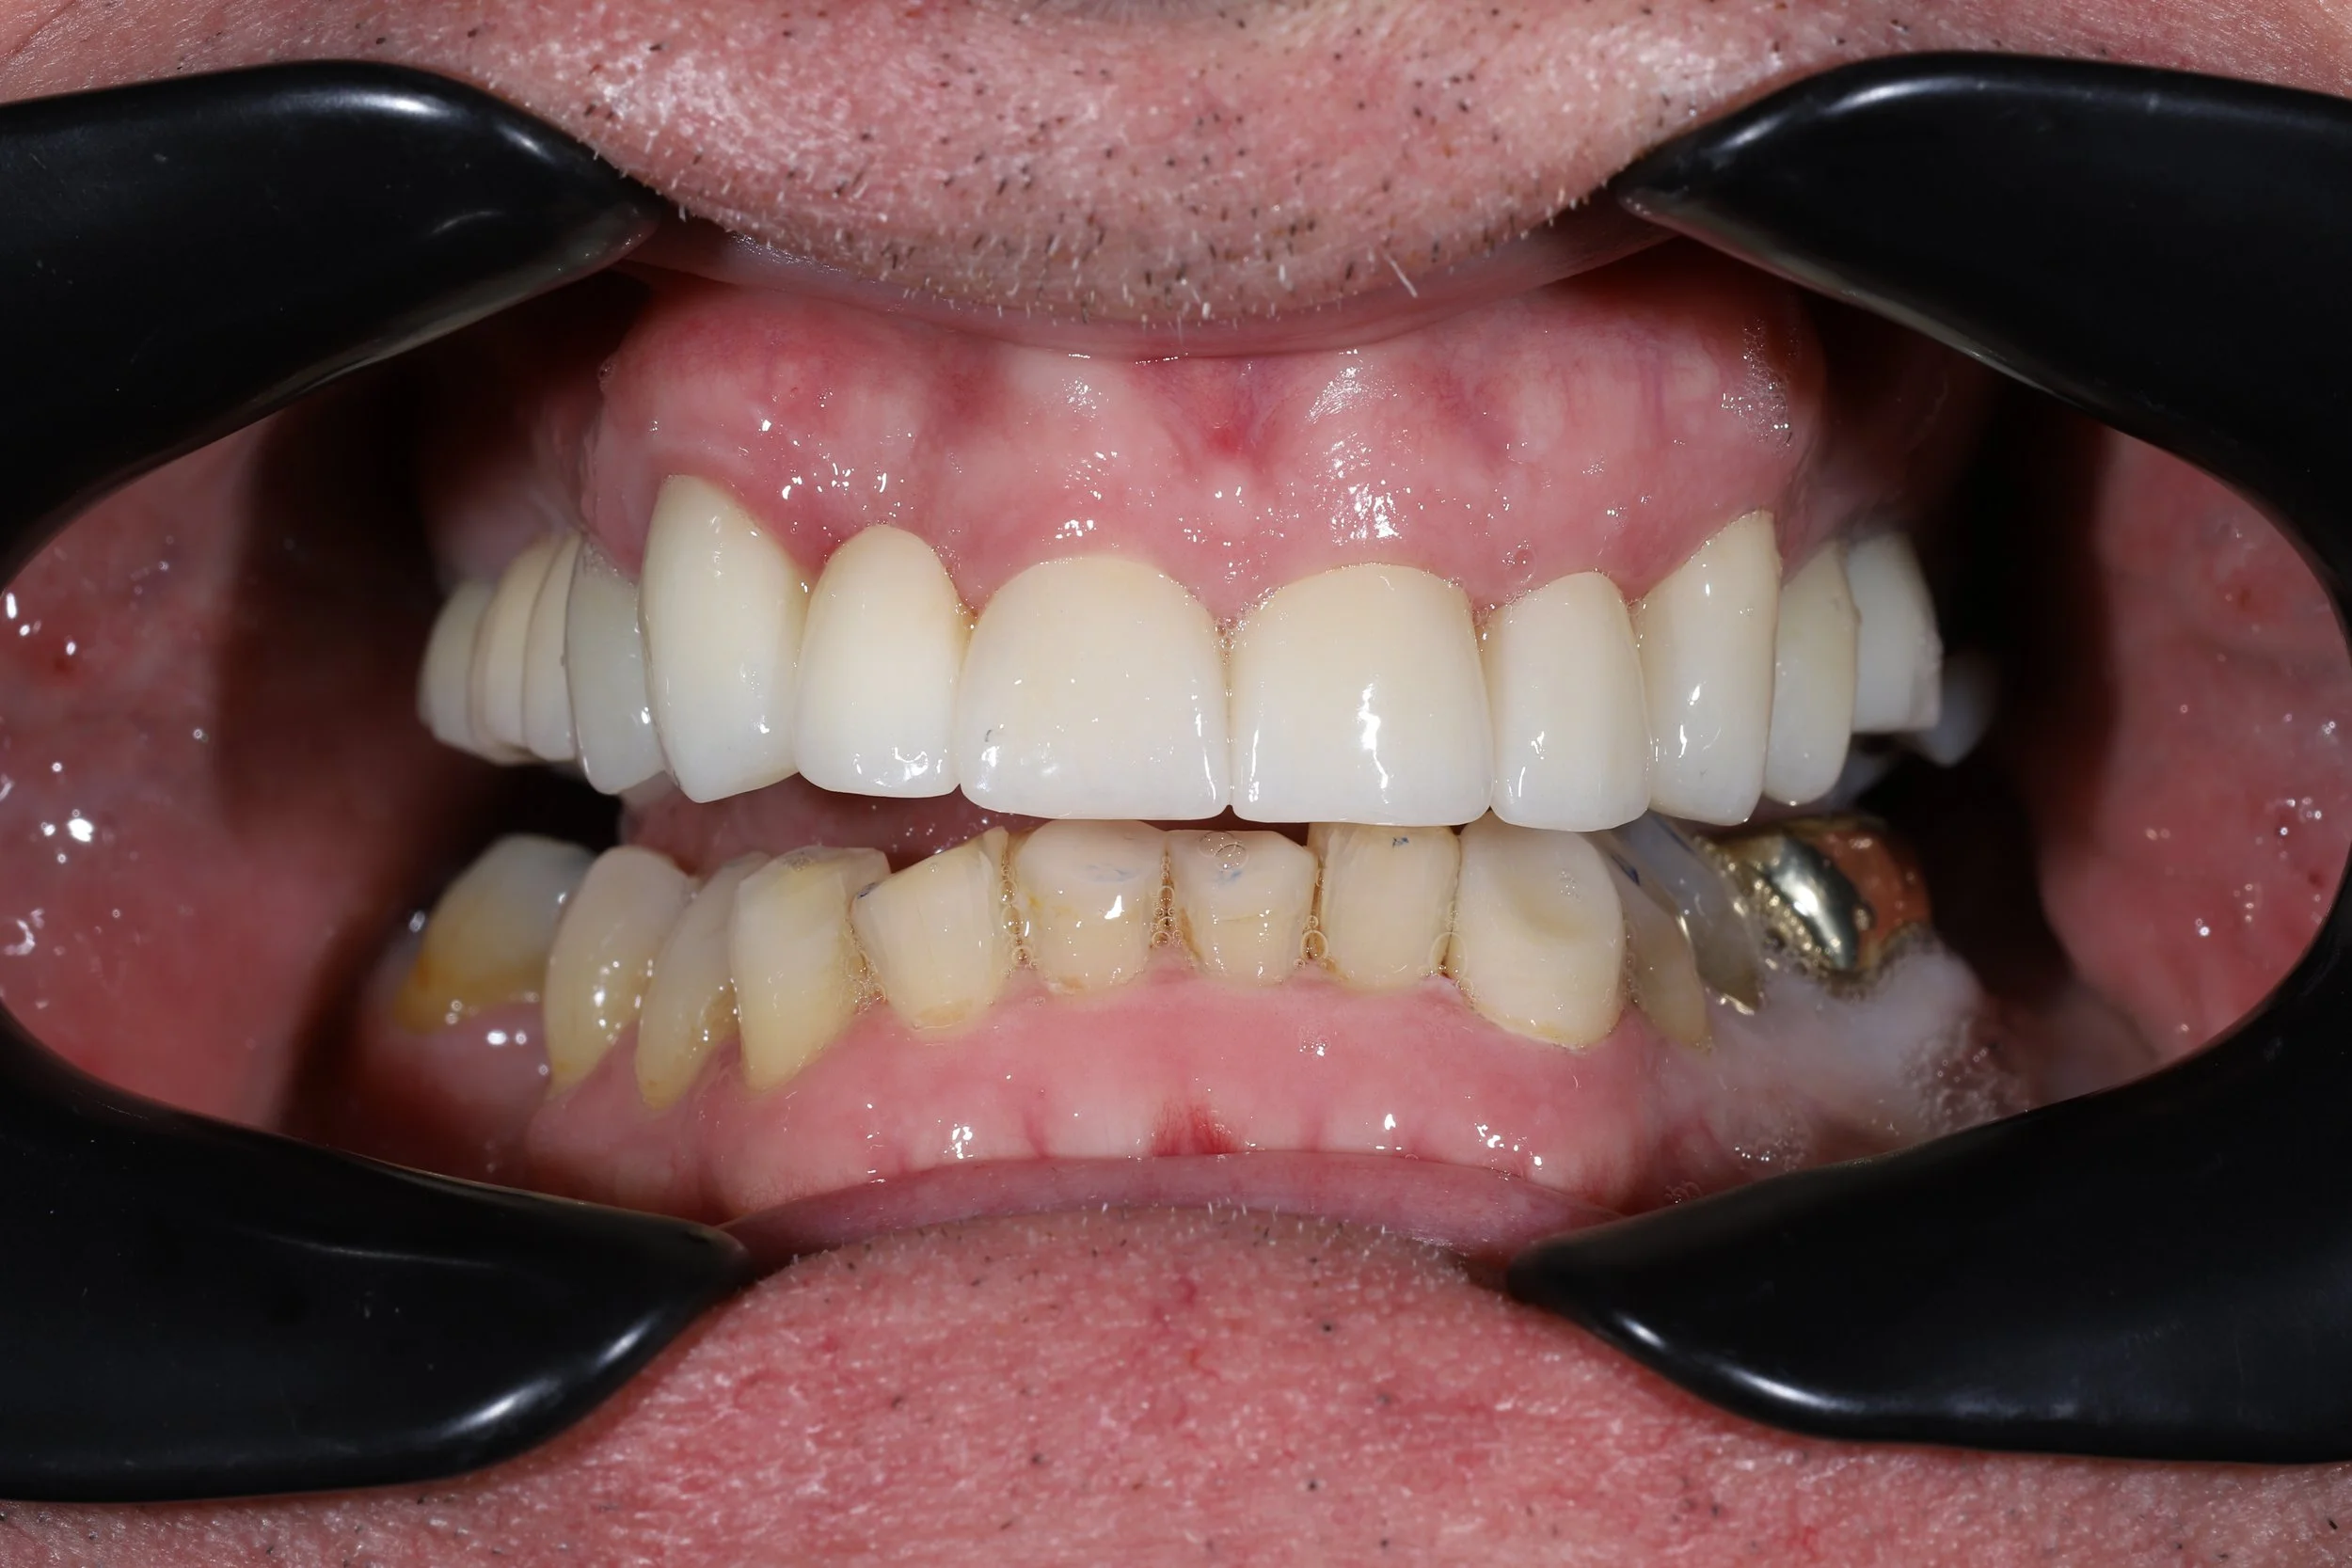

Examples of my work

Clinical cases with before and after photos

Throughout my 5 years at dental school I had bone grafts to move bone from my lower jaw to my upper jaw, placement of implants and bridges. Changes in my bite height and occlusion, eventually ditching my dentures by the age of 21.

You don’t have to be a dentist to see that my photo and x ray are different to most mouths.